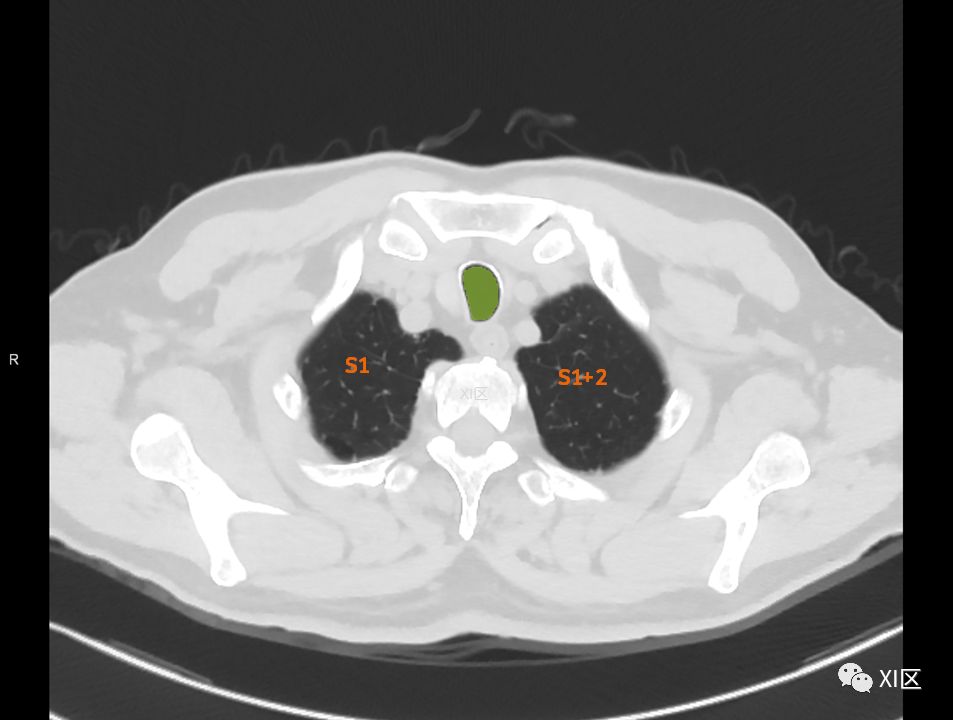

在进行肺的分段时,可以上下观察浏览,沿着相应气管的走形可以更容易准确地进行分段。

肺的断层分段示意图